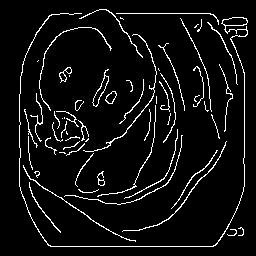

The performance metrics for Edgeconnect and AOTGAN on the validation data after fine-tuning the models, are shown in Table II. In addition to qualitative evaluation, Figure 3 provides example data from the different steps of the PolypConnect pipeline using the EdgeConnect model and the AOTGAN model. Due to obvious visual differences in the generated polyps between the models, we selected the EdgeConnect model as the main polyp inpainting model of the PolypConnect pipeline for further evaluation and qualitative assessment by domain experts.

Figure 3: Sample data used and generated in the different steps of PolypConnect pipeline. (a) - real polyp images, (b) - manually annotated polyp masks, (c) - randomly selected colon images used as input to the final step of PolypConnect, (d) - extracted edge images of row c. (e) - extracted edge images of polyp regions of row a using the masks of row b. (f) - combined edge images of row d and f. (g) - generated polyp on the images of row c using EdgeConnect. (h) - generated samples from AOTGAN.